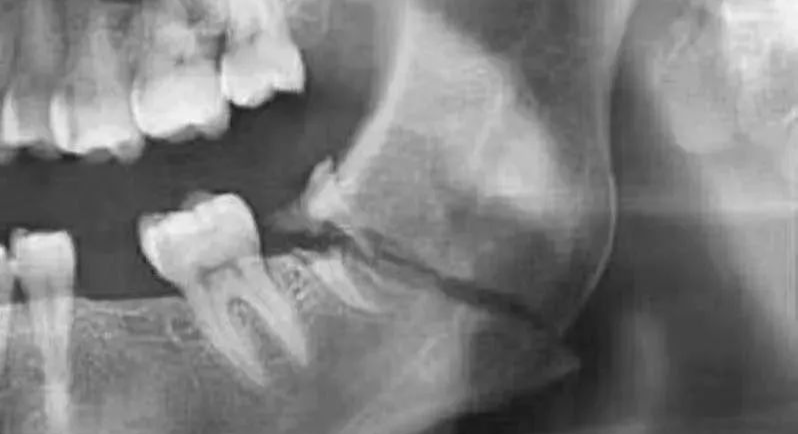

(2)阻生牙:可精确显示阻生牙的位置,与下牙槽神经管的关系,有无牙根弯曲,有无骨间隔,术前可预测术中损伤下牙槽神经的可能性。

口腔ct怎么拍摄【专科天地】没有口腔CT,你根本不会想到自己的牙齿长得多“奇葩”!_https://www.jmylbn.com_新闻资讯_第15张